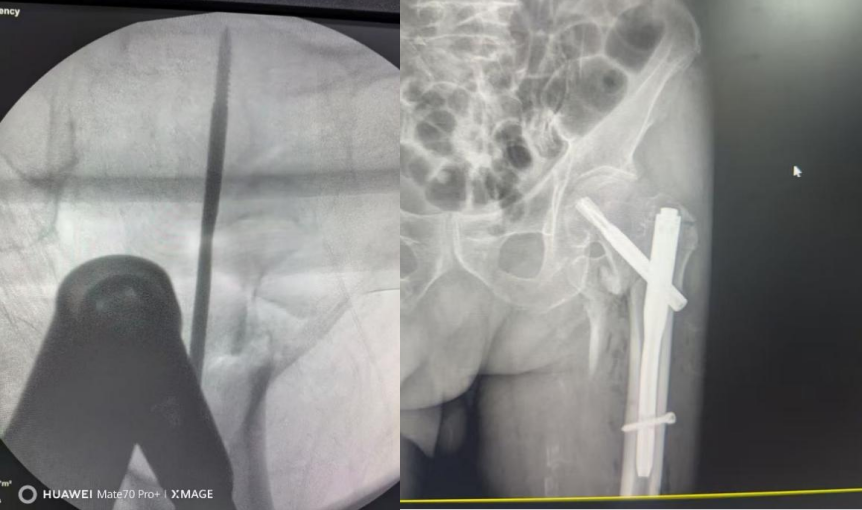

经过2个多小时的反复研判,专家们最终达成共识:在积极抗凝治疗、继续纠正贫血的基础上,抓住血栓的“时间窗口”,尽快实施微创PFNA术——股骨近端防旋髓内钉内固定术,这种微创手术创伤小、出血少、固定牢,尤其适合高龄骨折患者,能最大限度减少手术对老人身体的损伤。

手术团队在C型臂X线机透视下精准操作,从切口、插钉到锁定,每一个动作都稳、准、快。手术的关键在于既要快速完成骨折复位固定,减少创伤和出血;又要避免损伤周围血管神经,同时防范血栓脱落风险。

宋铁兵主任医师全神贯注操作,当最后一枚螺钉锁定完毕、手术顺利结束时,仅用了不到40分钟,手术切口小于5cm,出血量不到50ml。整个手术过程中,老人生命体征始终保持平稳。